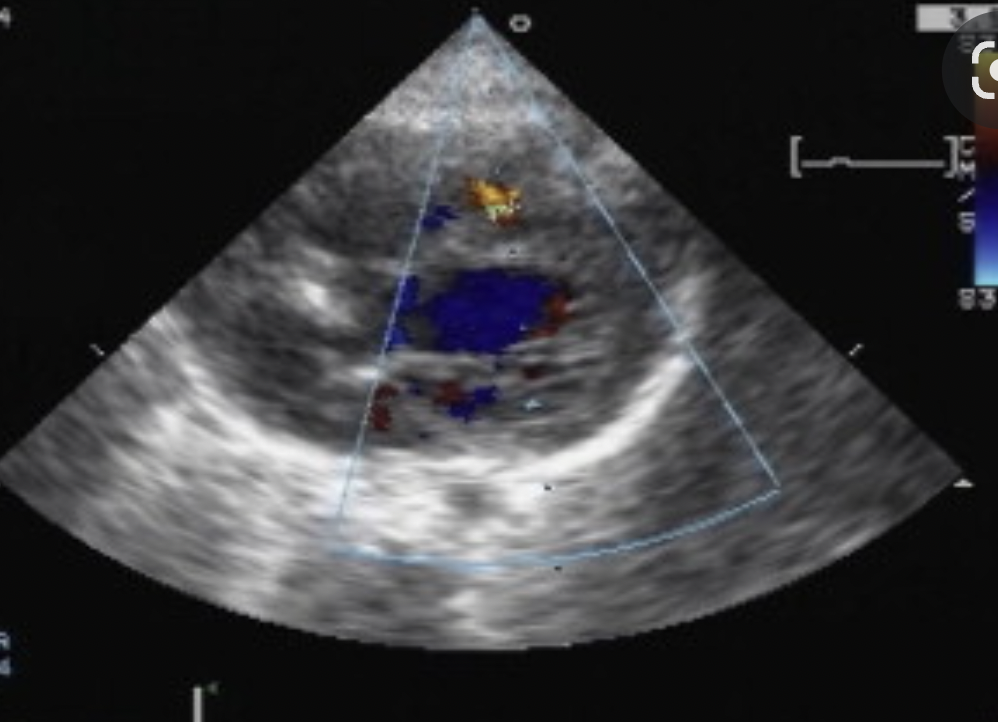

15

Q

What is this (be specific) ?

A

Peri-membranous VSD